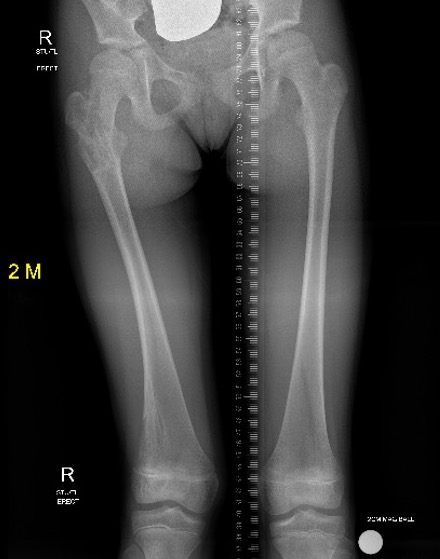

Growth disturbance

- leg length discrepancy

- bowing

Leg length discrepancy